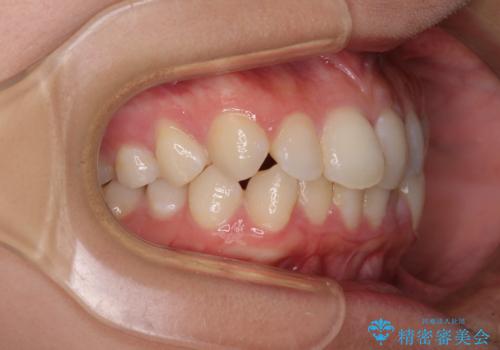

- 前歯のデコボコと歯肉に埋もれている奥歯を気にして来院された患者様です。

インビザラインでの治療を希望されていましたが、左右の下顎大臼歯が歯肉に埋もれており、特に右側は歯軸が顕著に傾斜していたため、インビザライン単独での治療は困難と判断し、ワイヤー装置を併用することとしました。

ワイヤー装置での下顎臼歯改善には時間がかかることが予想されたため、下顎のワイヤー矯正と並行して上顎をインビザラインで整え、その後インビザラインにより上下歯列を整える矯正治療を行うこととしました。